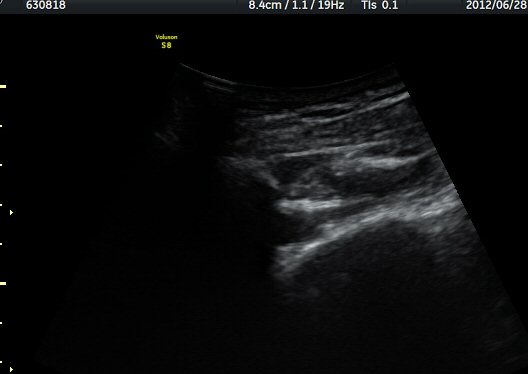

¾î±ú °üÀý µÚÂÊ ÈĹæ°üÀý¼ø Ⱦ´Ü¸é°Ë»ç¿¡¼­ °üÀý¼ø ³»Ãø, °¡½Ãµ¹±â°üÀý¼ø°í¶û(spinoglenoid

notch)¿¡¼­ Àú¿¡ÄÚ ³¶Á¾ÀÌ °üÂûµÈ´Ù(±×¸² 1). ŽÃËÀÚ¸¦ À§-¾Æ·¡ ¹æÇâÀ¸·Î º¯°æÇÏ¿© °üÂûÇÒ ¶§µµ

¿ª½Ã °ß°©°ñ °¡½Ãµ¹±â(spine) ¾Æ·¡¿¡¼­ Àú¿¡ÄÚ ³¶Á¾ÀÌ °üÂûµÈ´Ù(±×¸² 2). º¼·ÏŽÃËÀÚ·Î ¹Ù²Ù¾î °ü

ÂûÇÏ´Ï  °¡½Ãµ¹±â°üÀý¼ø°í¶û¿¡¼­ Àú¿¡ÄÚ ³¶Á¾ÀÌ ´õ¿í ¶Ñ·ÈÈ÷ °üÂûµÈ´Ù(±×¸² 3, 4).